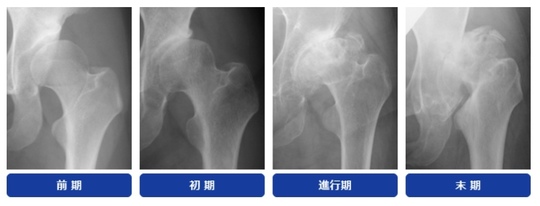

年代が若い時の股関節の悩みは、写真の左側になる。

右側は変形が進み『手術』という言葉が選択肢として出てくる。

若い年代での股関節の問題は、将来的にみれば変形性股関節症に移行する可能性はおおくあります。